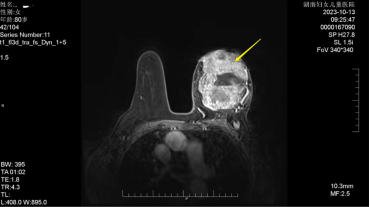

邹奶奶(化名),80 岁高龄,曾因骑车受伤导致双下肢行走困难,2019 年底,她发现左乳外上象限有一乒乓球大小的肿块。由于疫情的影响,未能及时就医,肿块逐渐增大,到了 2023 年初,肿物已突出皮肤表面并伴有红肿,即将破溃,一旦破溃,将流水、流血、流脓、感染、散发恶臭。

2023 年 4 月至某院行肿物穿刺,诊断为左乳浸润性癌,尽管接受了口服化疗药物(卡培他滨)治疗,但因副作用太大(口腔炎、手足红斑溃烂等),疗效不佳,她不得不选择停止服药。

因高龄伴随心脏病、高血压、糖尿病、腿脚不便长期卧床、肿块巨大、即将破溃、缺皮等,多家医院不建议进行手术和放化疗治疗。